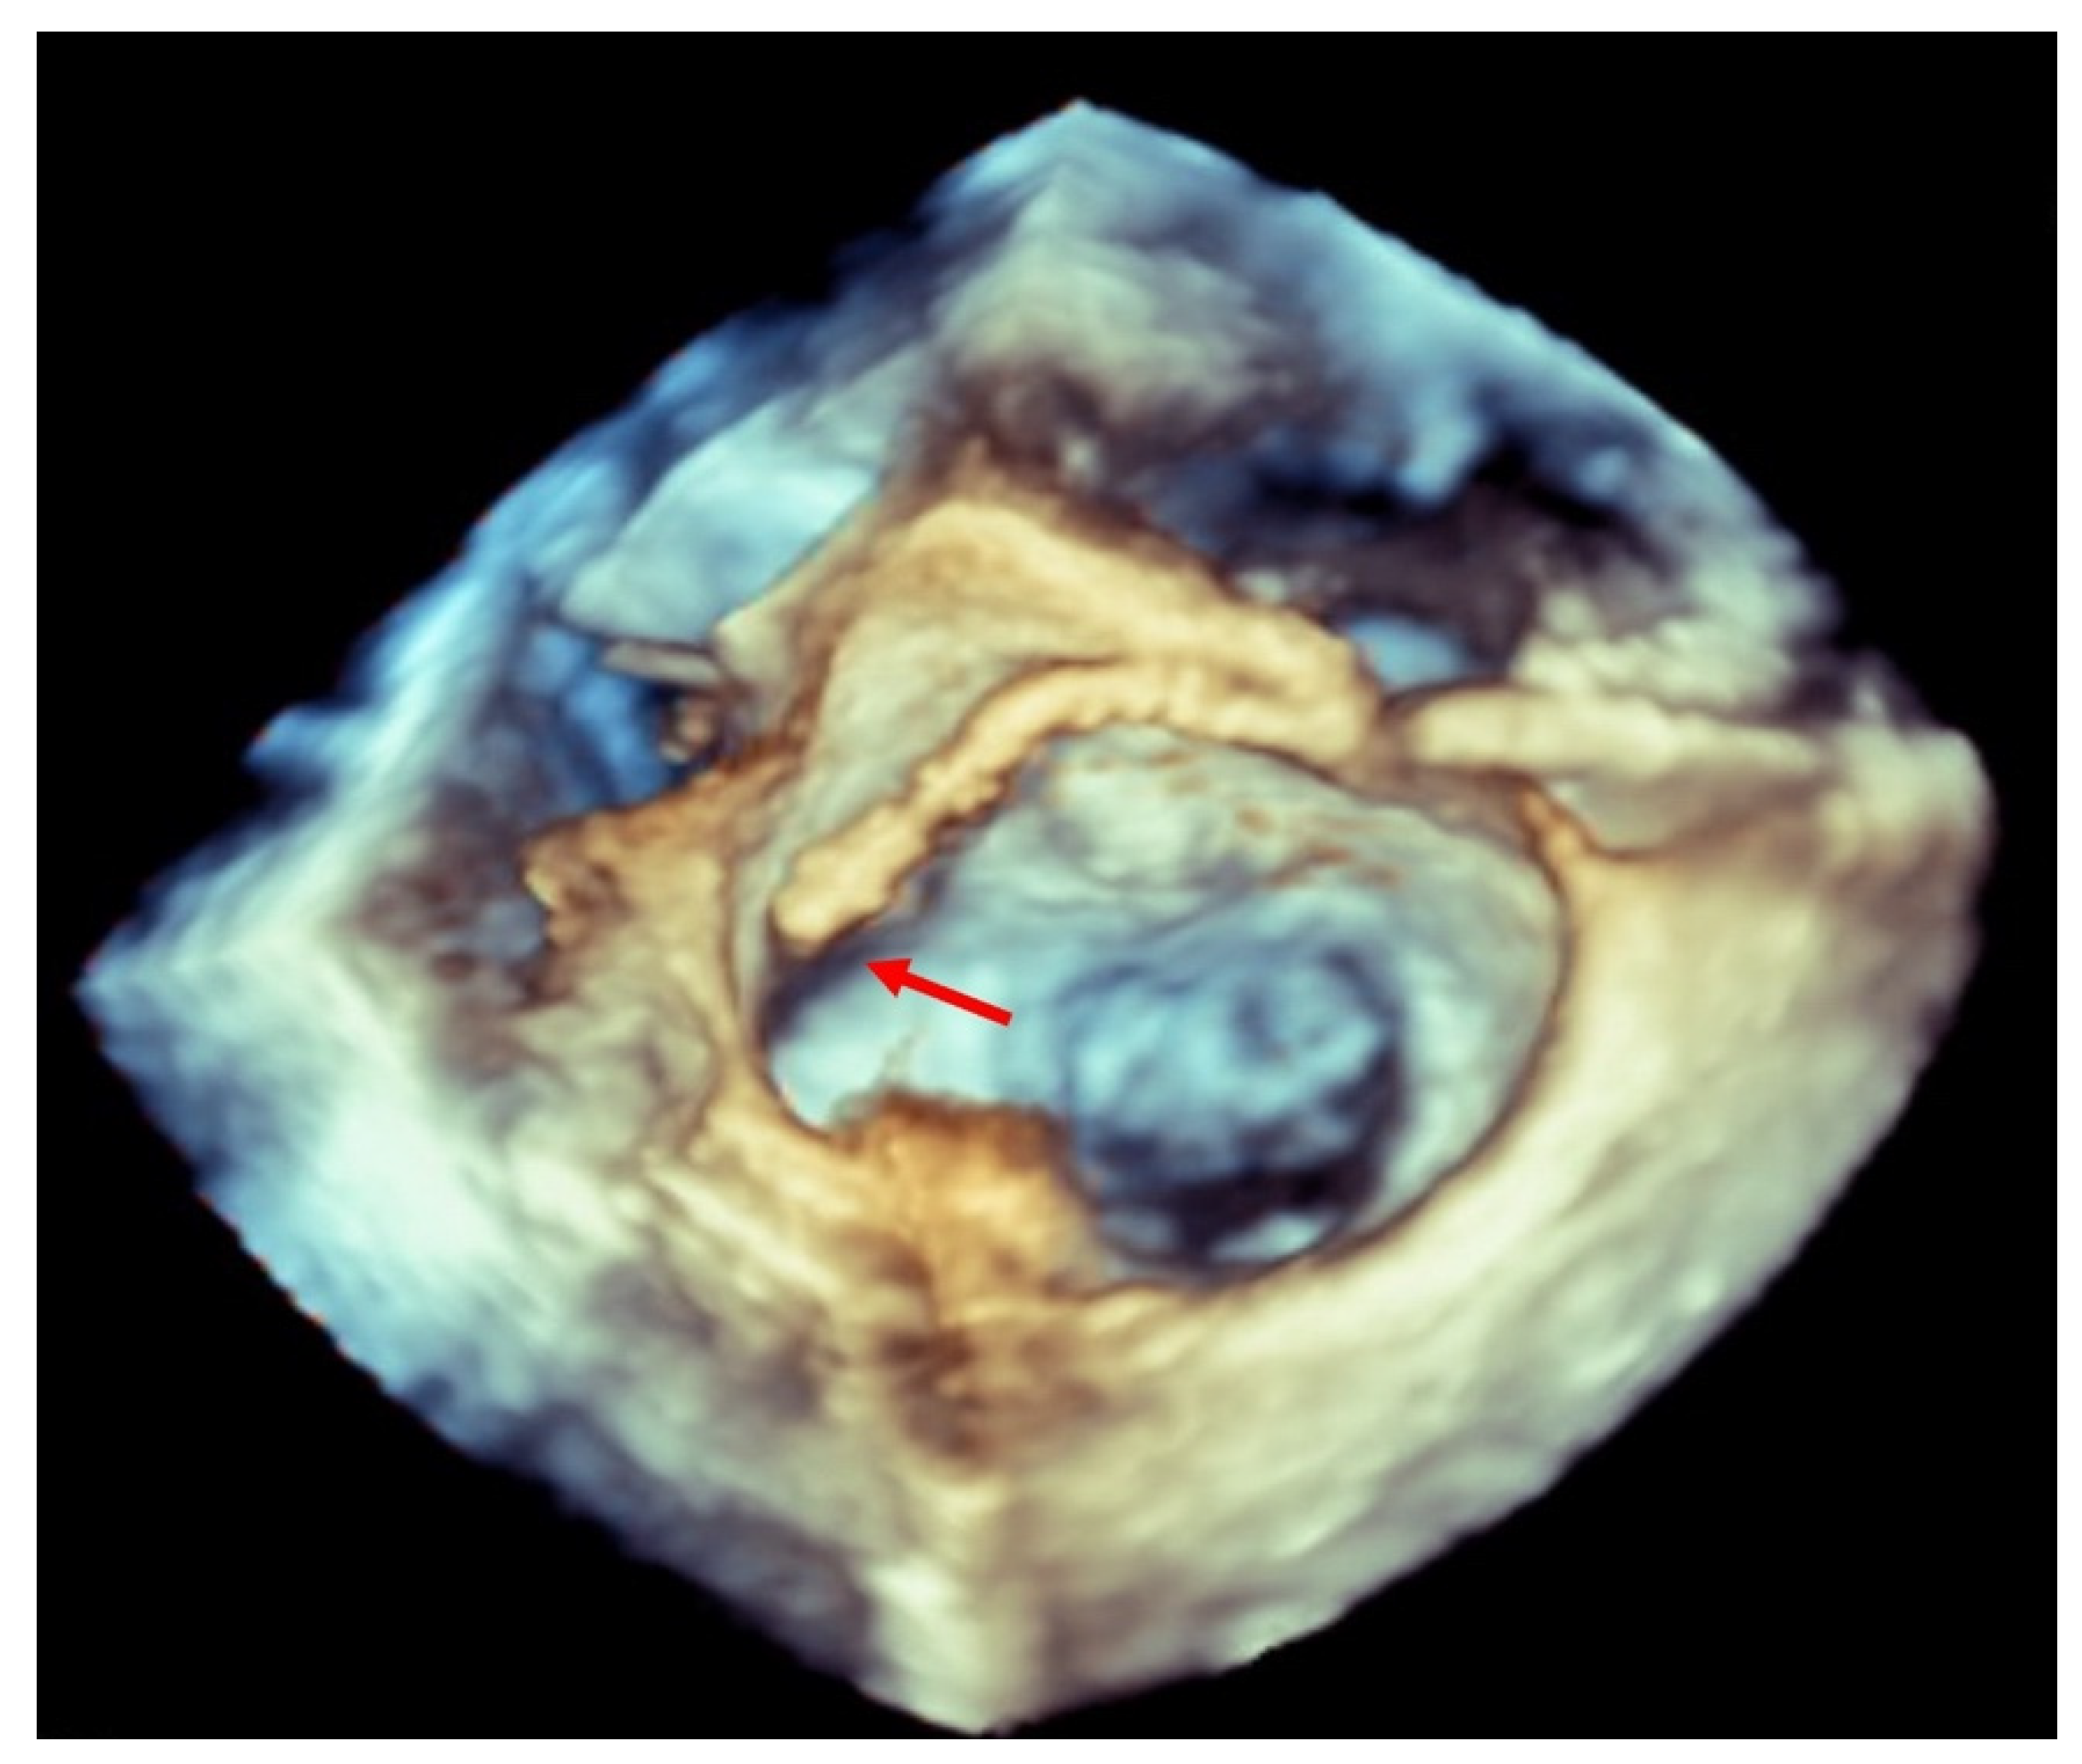

Figure 1.

Three-dimensional transesophageal echocardiogram showing a clip inside the left atrium touching the lateral wall (red arrow).